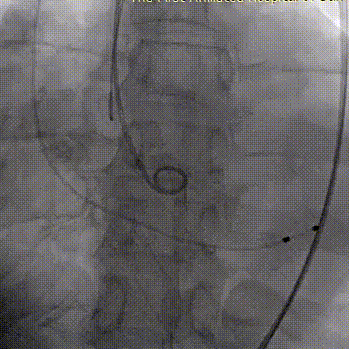

2026年伊始,TaurusTrio经导管主动脉瓣系统在复旦大学附属中山医院,浙江大学医学院附属第二医院,中国医学科学院阜外医院,首都医科大学附属北京安贞医院,四川大学华西医院等多家临床中心成功开展上市后全国首批植入。这不仅是TaurusTrio正式走向广泛临床应用的重要里程碑,更标志着中国单纯主动脉瓣反流介入治疗正式迈入了“心键合璧”的全新纪元。